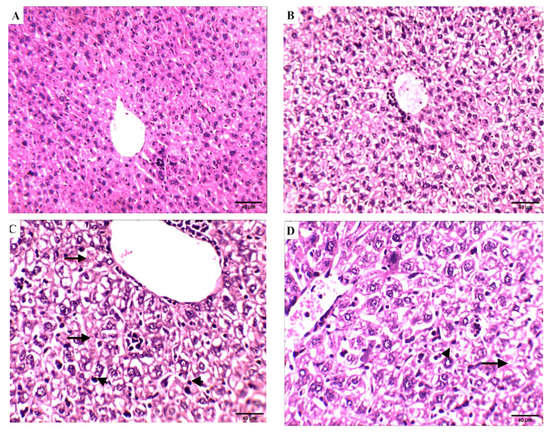

Effect of Compound 4 on the Liver Tissue of SEC-Bearing Mice

The effect of compound 4 treatment on hematological and biochemical parameters was demonstrated through liver histopathological examination (Figure 8). Liver tissue from normal control mice showed a normal anatomical structure of liver lobes and polyhedral hepatocytes with a nucleus and granular cytoplasm. Hepatocytes arranged in alternating strands with blood sinusoid forming a network around the central vein, and liver sections of normal control mice treated with compound 4 showed normal-looking liver lobules; some hepatocytes showed a hydropic degeneration and a balloon degeneration. On the other hand, degenerated balloons were visible in the SEC control group with cytoplasmic vacuolation, intranuclear cytoplasmic inclusions, and absence of cell boundaries, and liver tissue loss of membrane integrity leads to cell fusion. Hydropic degeneration of the hepatocytes and other hepatic cells had nuclear pyknosis (arrowheads) and karyolysis. Hydropic degeneration of hepatocytes, nuclear pyknosis, and karyolysis still occurred in the 5-FU group in the SEC group. On the contrary, the SEC group + compound 4 group showed liver lobules looking normal. In addition, few hepatocytes showed hydropic degeneration and activated Kupffer cells. These findings support the results previously seen after tumor volume measurement, which indicates that mice treated with compound 4 were more efficient at inhibiting tumor growth.

Figure 8.

Effect of compound 4 on the liver tissue of SEC-bearing mice: (A) normal control, (B) normal group treated with compound 4. (C) SEC control group, shows nuclear pyknosis (arrowheads) and karyolysis (arrows). (D) SEC mice treated with 5-FU still exhibit hydropic degeneration of hepatocytes, nuclear pyknosis (arrowheads), and karyolysis (arrows). (E) SEC mice treated with compound 4 (H&E stains, magnification ×200). Quantification data of the H&E analysis of liver are supported in Supplementary Table S2.